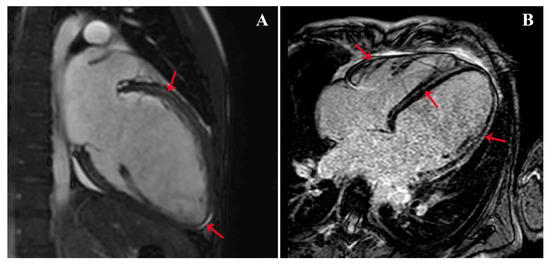

- We presented a case of new onset dilated cardiomyopathy (DCM) with renal infarction in a young man on a treatment with high-dose isotretinoin.

- Possible known causes of DCM using a complete cardiac imaging assessment, genetic testing, and laboratory analysis have been ruled out.